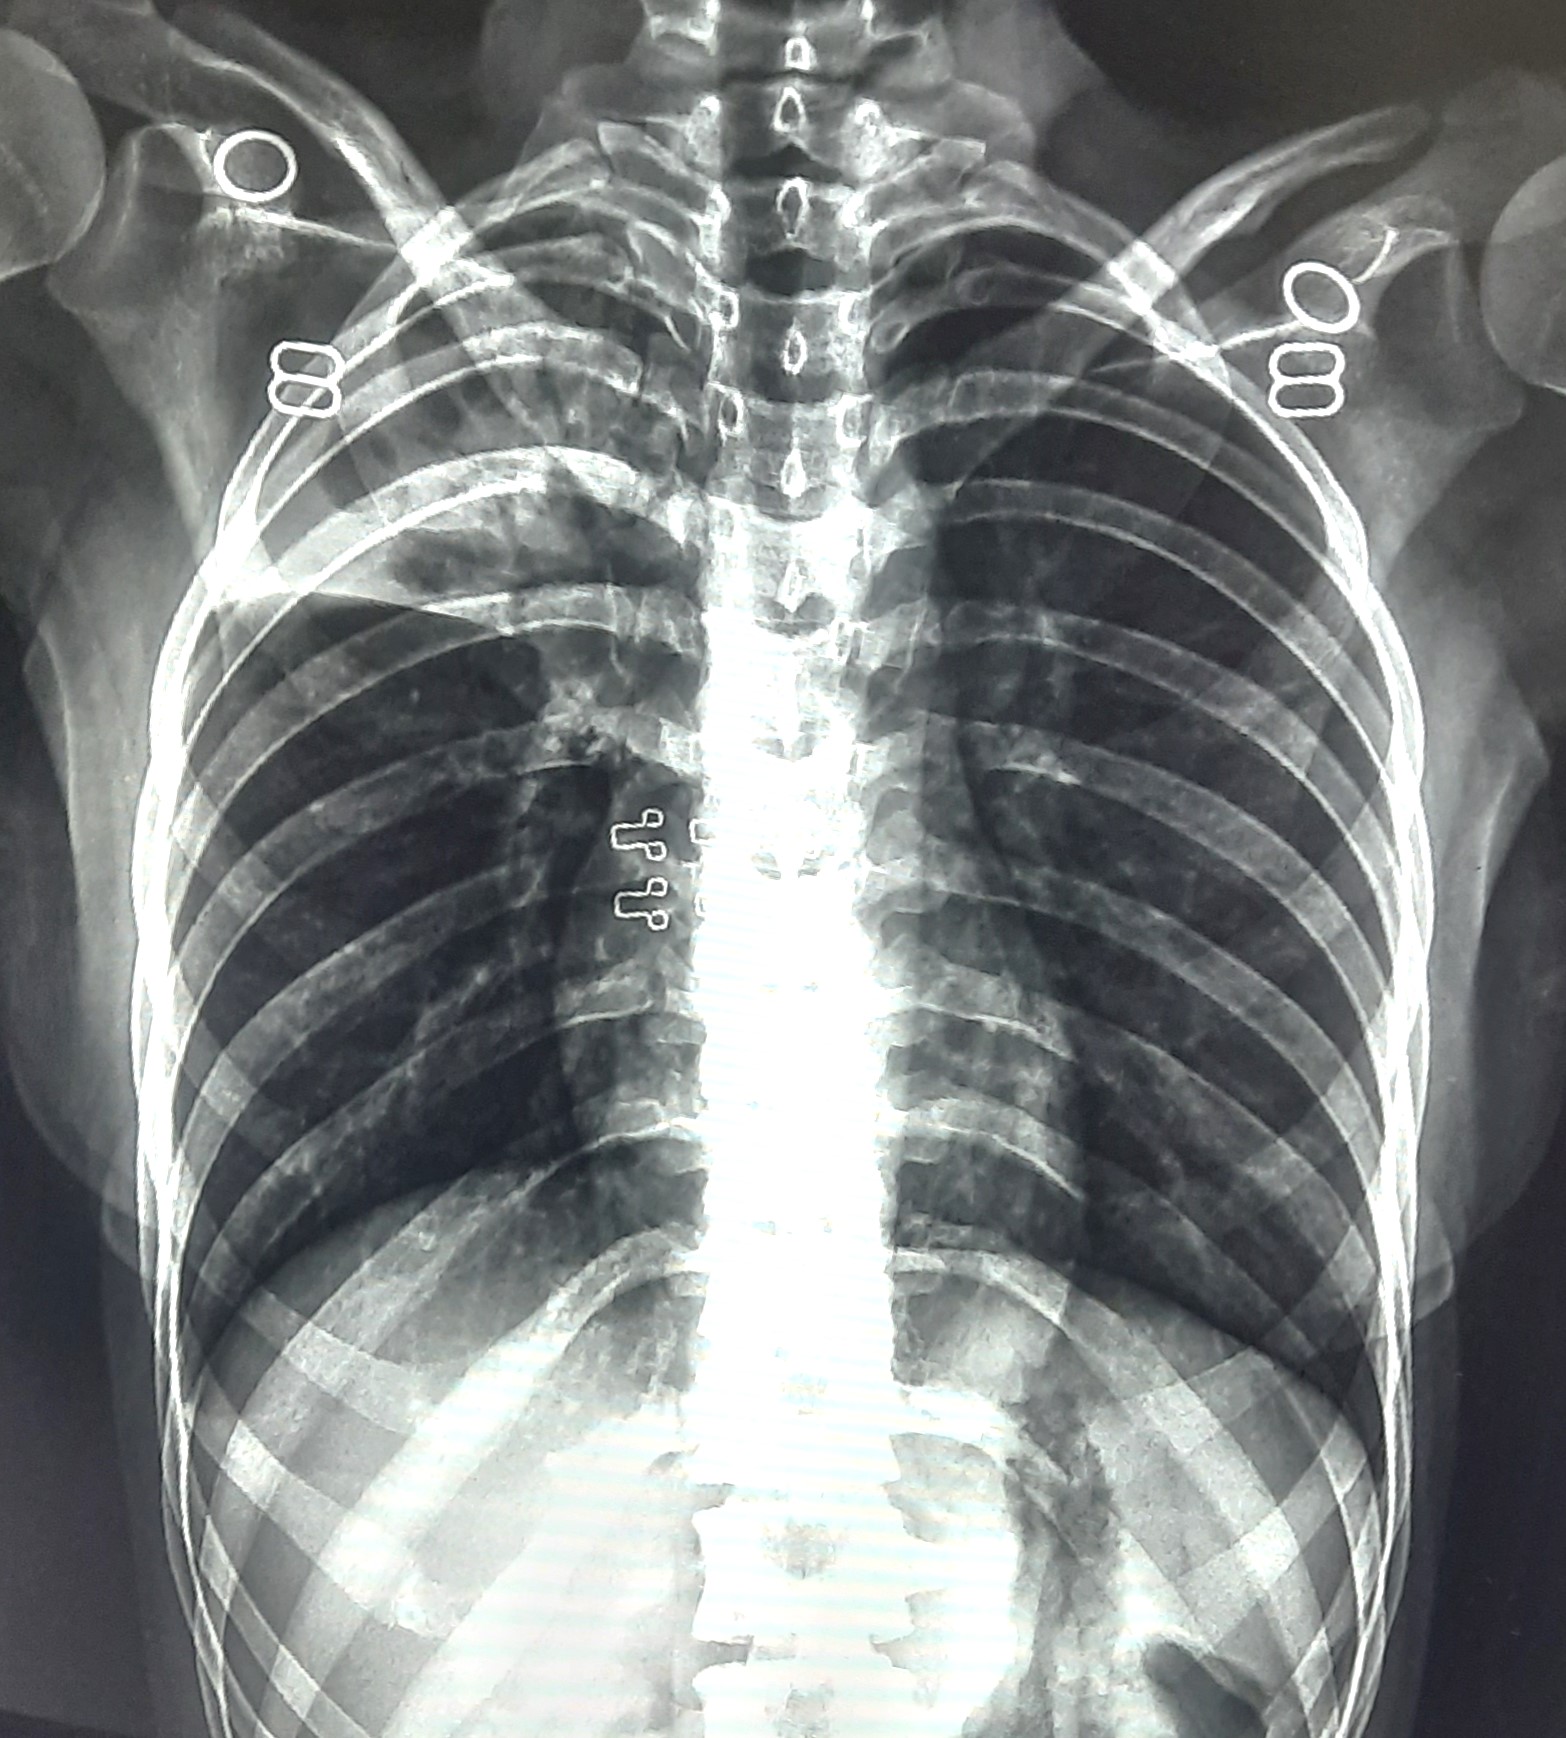

| 84 | IGGMC, Nagpur, Nagpur | P2 | 29-4388 | Dipak Panchbudhe | Consent taken on Paper | 33 Yrs. |

Provisional Diag : Pulmonary Tuberculosis Reactivation ?

Final Diag : Pulmonary Tuberculosis |

TB Case (Confirmed) | Bilateral multiple ill-defined alveolar opacity present, Left Sided Upper Zone Fibro Cavitary Lesion Present | Abnormality visible on x-ray |